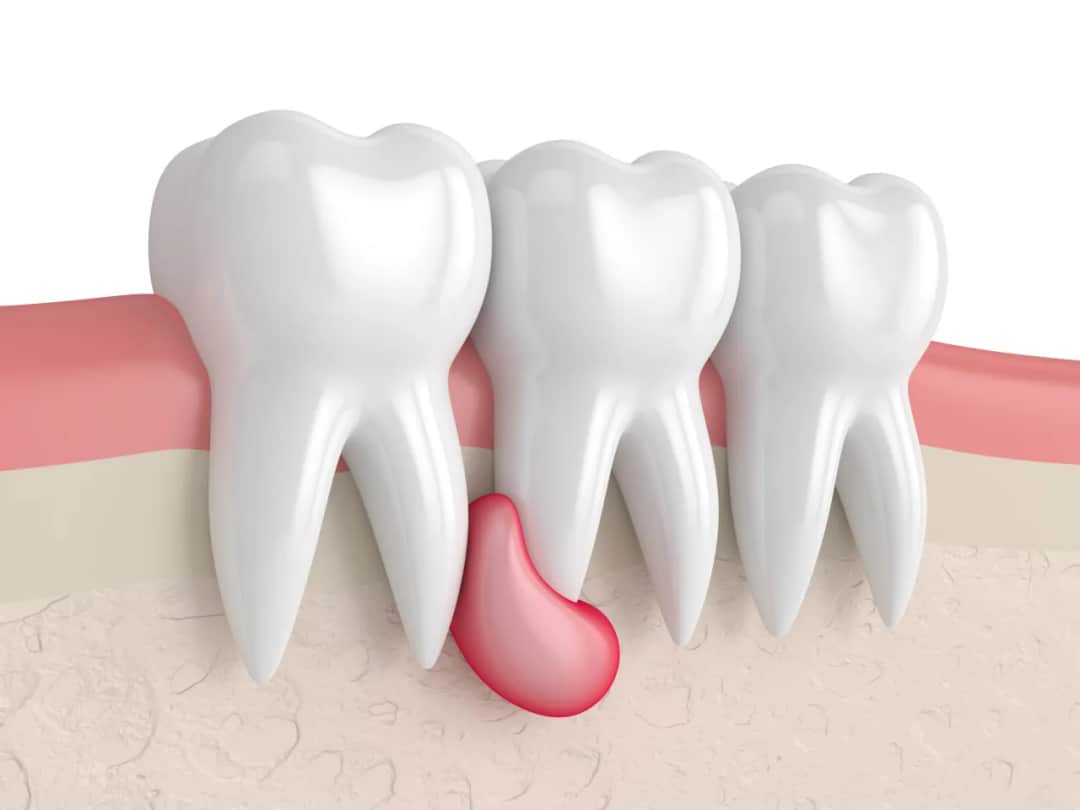

Masz torbiel na dziąśle? Dowiedz się, jak wygląda, jakie daje objawy i czy jest groźna. Poznaj skuteczne metody leczenia i diagnozy. Sprawdź!